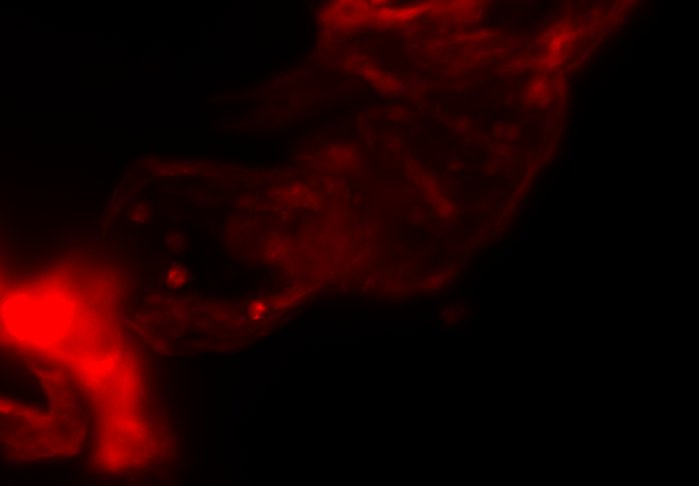

The combination of prospective optical gating for real-time phase matching and prospective optical gating for long-term phase locking allow us to capture in phase images over extended periods of times. Figure 4 demonstrates this phase locking over 18+ hours across a key developmental phase - heart looping.